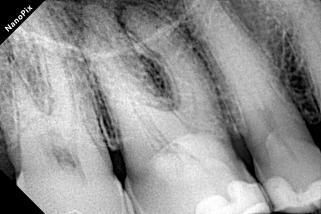

Patient Info:A 65-year-old patient presented with biting pain and a buccal sinus tract (fistula) on the right maxillary first molar (Tooth 16).

Radiograph:Radiolucency at the apex of the mesiobuccal (MB) root; severe calcification in the pulp chamber and the coronal third of the canals.

Diagnosis:Chronic apical periodontitis with a sinus tract; Severe pulp calcification.